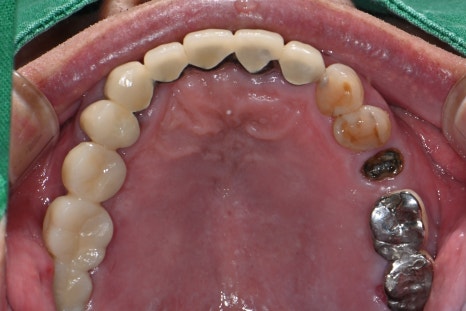

-치료 후

왼쪽 사진: #25-27 보철물 완성 후 촬영한 파노라마 엑스레이 입니다.

오른쪽 사진: 자연치아처럼 심미적이고 튼튼한 지르코니아로 보철 마무리 되었습니다.